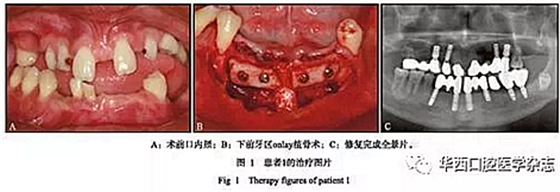

患者1,男,17歲,口內(nèi)檢查示:12、13、14、15、17牙,22、23、24、25、27牙,31、32、33、35、36、37牙,41、42、43、44牙缺失;52、53、63、65、81、 82乳牙滯留;38牙埋伏阻生。11、21牙畸形異位,間隙較大,左上頜側(cè)切牙區(qū)及下頜前牙區(qū)牙槽骨極窄,呈刃狀,右上頜前磨牙區(qū)骨量較窄,腭側(cè)骨缺損明顯(圖1A)。

治療過程:

1)分別行右上頜前磨牙區(qū)及下前牙區(qū)onlay植骨術(shù),下頜前牙區(qū)取頦部自體骨塊(圖1B),避免開辟第二術(shù)區(qū),減輕患者痛苦,術(shù)中拔除滯留乳牙52、53、81、82;

2)避開22、23牙位點(diǎn),于24牙位點(diǎn)行經(jīng)牙槽嵴頂上頜竇提升術(shù)同期植入種植體1枚,行21—24牙(三單位)烤瓷橋修復(fù),降低手術(shù)難度,減小手術(shù)風(fēng)險(xiǎn),術(shù)中拔除滯留乳牙 63、65;

3)正畸轉(zhuǎn)診評(píng)估后,因牽引易導(dǎo)致11、21牙松動(dòng)脫落,故行烤瓷冠修復(fù)關(guān)閉其間隙,而患者為低笑線型患者,降低了美學(xué)風(fēng)險(xiǎn);4)12、13、24、25、31、33、35、36、41、43牙位共植入10枚種植體;5)利用16、47、46牙穩(wěn)定的咬合關(guān)系,分階段進(jìn)行永久修復(fù),根據(jù)右側(cè)天然恒牙正常的咬合高度修復(fù)左側(cè)后牙,左側(cè)后牙修復(fù)完成后再進(jìn)行右側(cè)后牙修復(fù),最后進(jìn)行前牙修復(fù)。分階段的修復(fù)方式降低了修復(fù)復(fù)雜性,避免了咬合重建,患者肌肉關(guān)節(jié)適應(yīng)良好,最終完成上部修復(fù)(圖1C)。